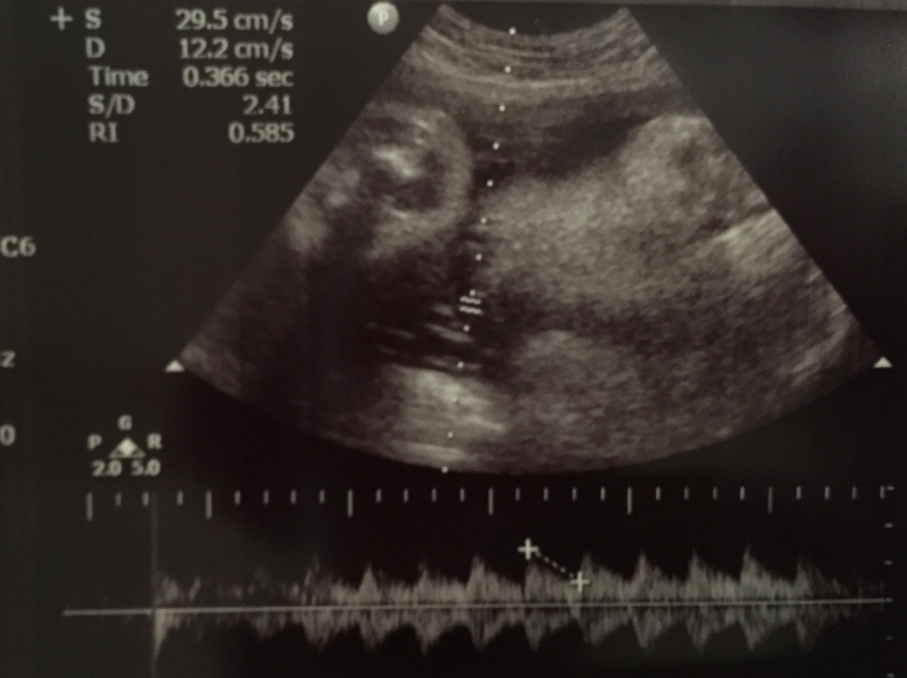

除咗size之外,我哋仲check check臍帶血流嘅情況,都係正常範圍之內,good﹗